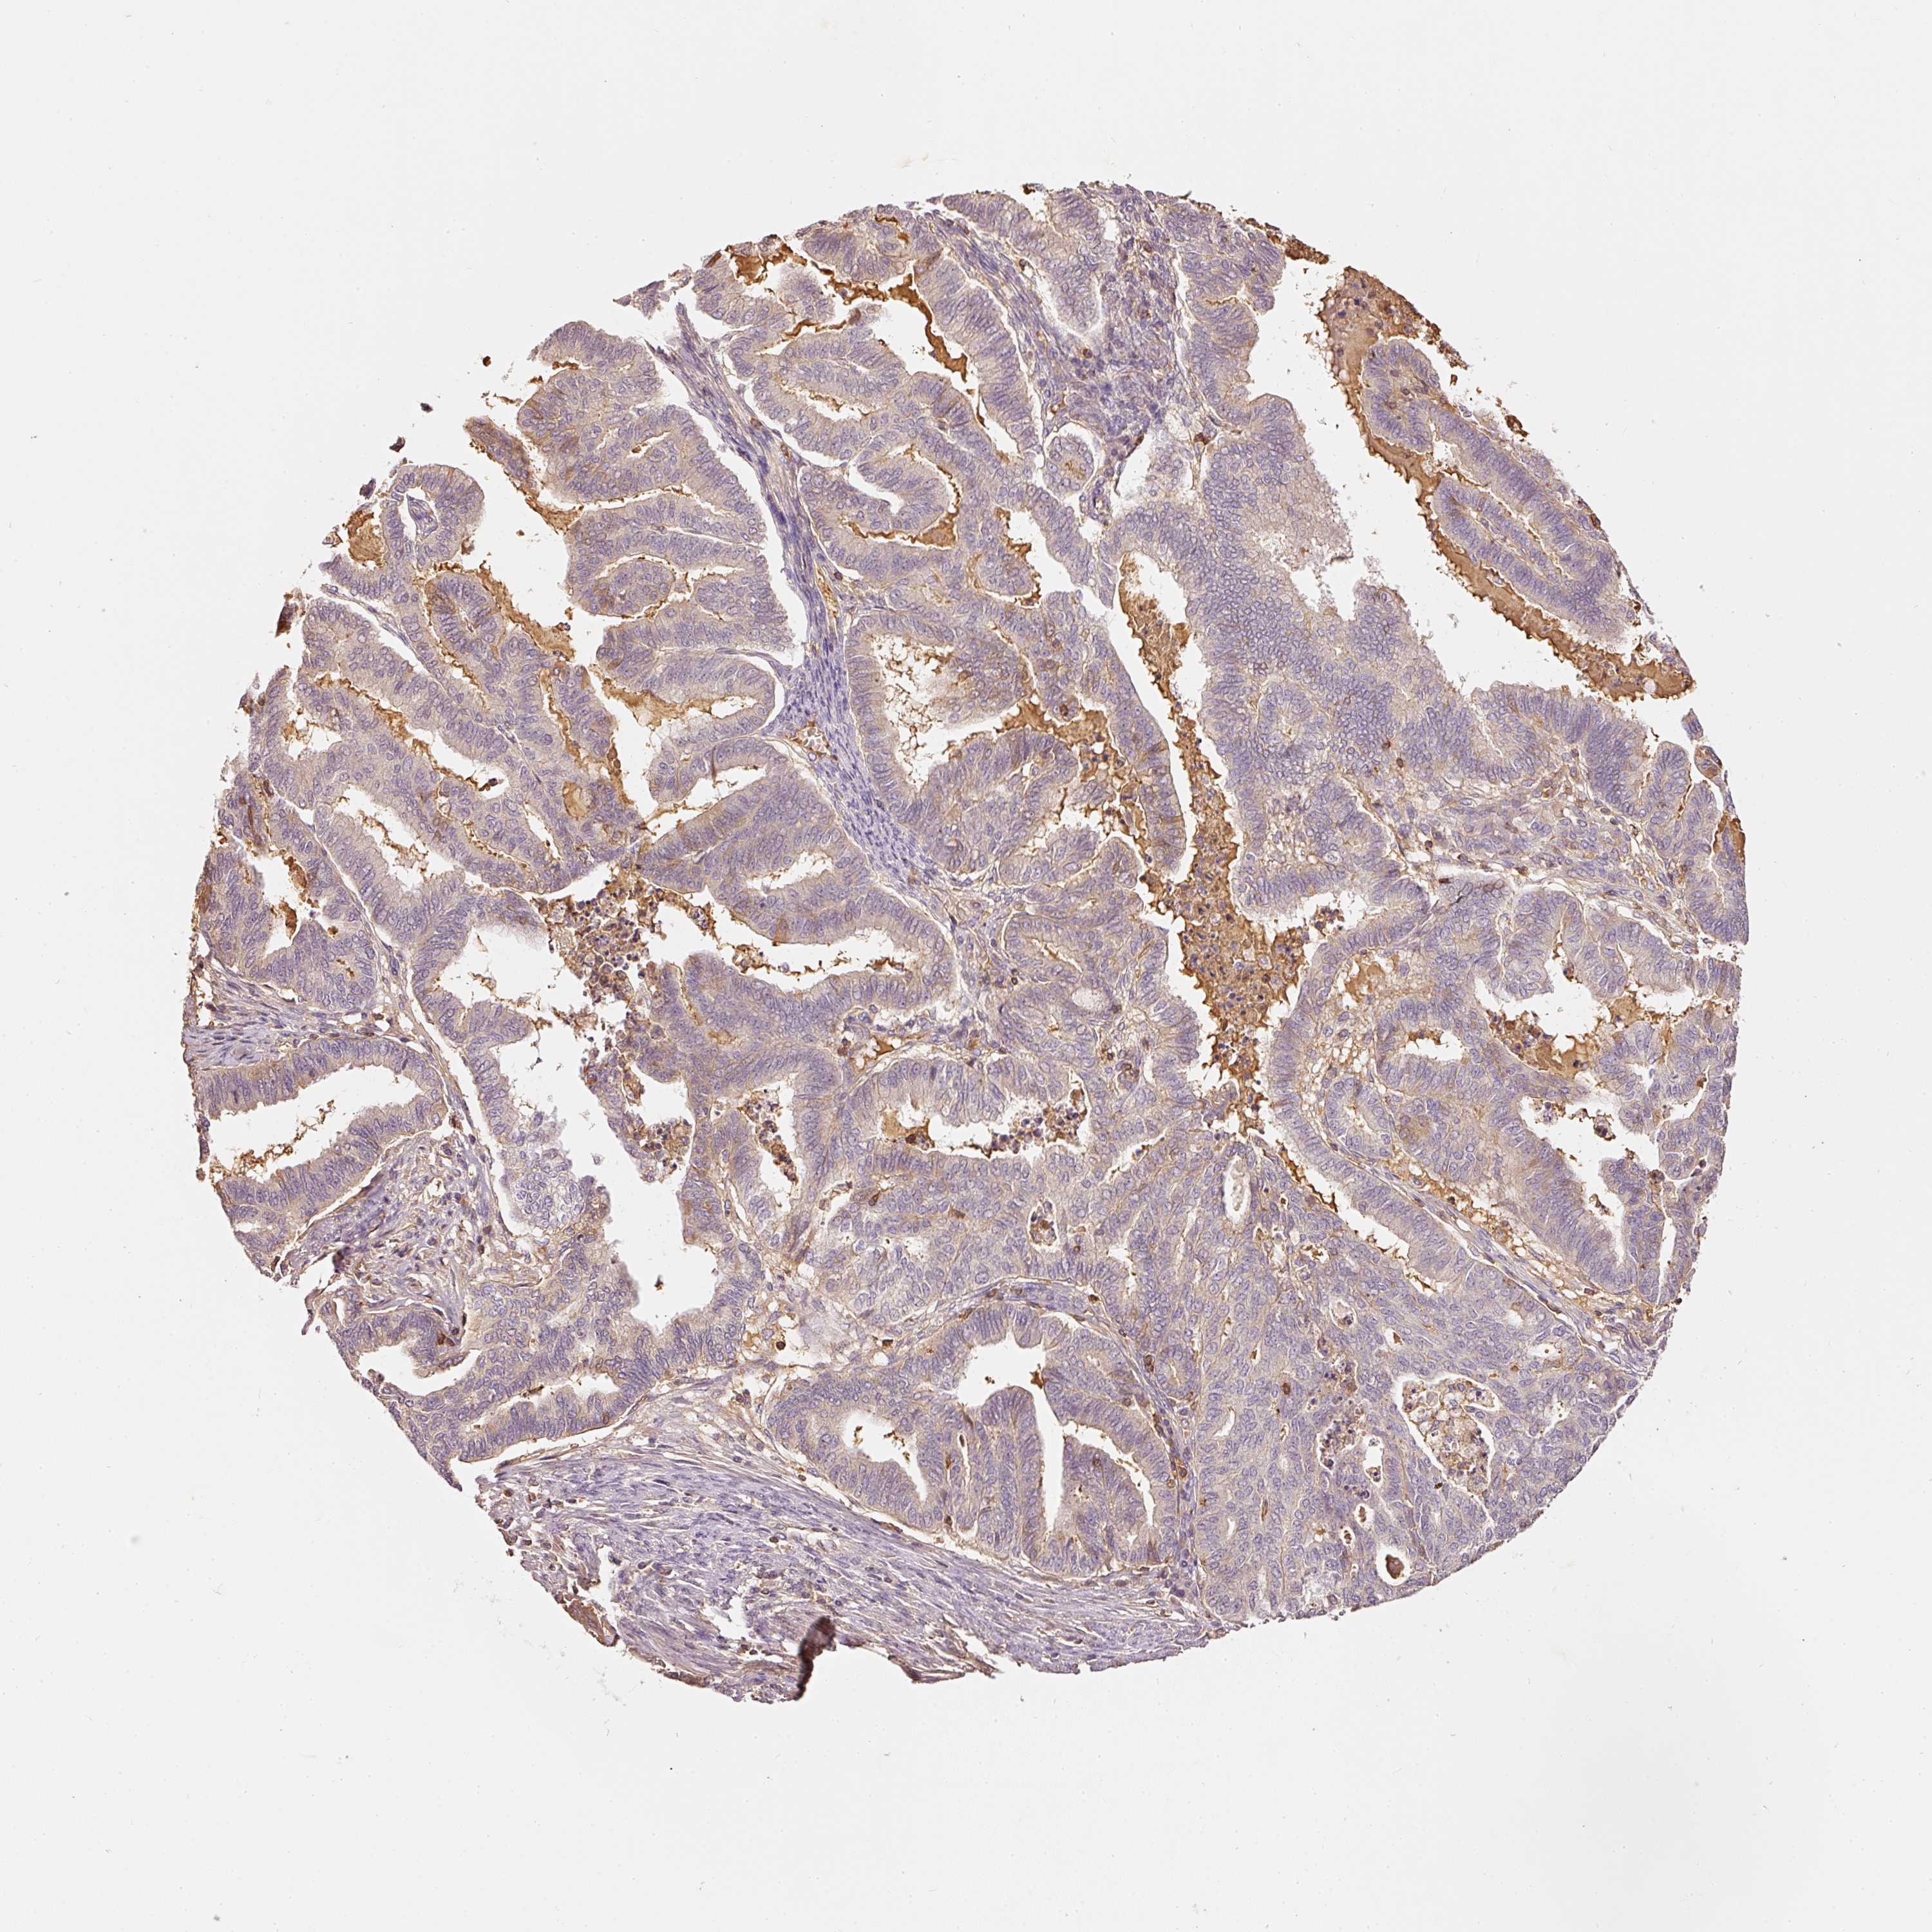

ENDOMETRIAL CANCER - Protein expressioni

A mouse-over function shows sample information and annotation data. Click on an image to view it in a full screen mode. Samples can be filtered based on level of antibody staining by selecting one or several of the following categories: high, medium, low and not detected. The assay and annotation is described here.

Note that samples used for immunohistochemistry by the Human Protein Atlas do not correspond to samples in the TCGA dataset.

Antibody stainingi

Antibody staining in the annotated cell types in the current human tissue is reported as not detected, low, medium, or high, based on conventional immunohistochemistry profiling in selected tissues. This score is based on the combination of the staining intensity and fraction of stained cells.

Each image is clickable and will lead to virtual microscopy that enables deeper exploration of all samples and also displays staining intensity scores, fraction scores and subcellular localization as well as patient and tissue information for each sample.

Antibody HPA018849

Antibody HPA019536

Antibody CAB033987

Staining

High

Medium

Low

Not detected

Intensity

Strong

Moderate

Weak

Negative

Quantity

>75%

75%-25%

<25%

None

Location

Nuclear

Cytoplasmic/membranous

Cytoplasmic/membranous,nuclear